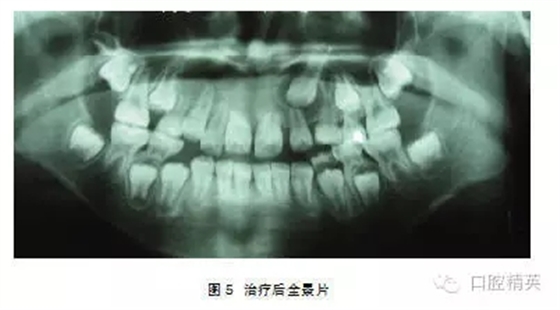

典型病例1: 患者,男,10歲,因左上前門牙未萌出于2009年10月來上海第九人民醫(yī)院預(yù)防、兒童口腔科就診。檢查: |1未萌,1| 全萌,1|2之間間隙為4mm。牙片及全景片示: |1骨內(nèi)埋伏,1| 2之間有埋伏多生牙,多生牙與 |1的重疊,不能清晰顯示多生牙和 |1在頜骨中的具體方位及相關(guān)關(guān)系(圖1-2),采用CBCT掃描后,圖像能清晰顯示多生牙和 |1的形態(tài)、大小、數(shù)目、牙根發(fā)育情況、在頜骨中具體位置、萌出方向及相互關(guān)系(圖3-4),經(jīng)手術(shù)證實情況與CBCT圖像顯示完全一致,手術(shù)拔除多生牙, |1作外科開窗術(shù)+正畸牽引治療。

典型病例2:患者,女,10歲,因1|未萌來我院就診(圖1)。

檢查:1|未萌, |1全萌, 2|1之間間隙為5mm。X線示:1| 骨內(nèi)埋伏,倒置,牙冠的舌側(cè)向外,彎根。 |1牙根已形成。(圖2、3)。

處理:2004年3月行外科開窗+正畸牽引治療,7個月后檢查:1|已萌出,未完全到位,1|唇側(cè)牙根處稍隆起,即為彎曲的牙根。因1|為彎根比較嚴重,如完全排齊有可能使牙根暴露,故未完全排齊(圖4、5)。

典型病例3:患者,男,11歲,因—1未萌來我院就診(圖1)。

檢查: |1未萌,1|全萌,1|2之間間隙為5mm。X線片示: |1骨內(nèi)埋伏,倒置,埋伏牙倒置角度在130°,牙冠的腭側(cè)面向外,稍彎根,1| 牙根基本形成(圖2~4)。

處理:行外科開窗+正畸牽引治療,6個月后破齦萌出,連續(xù)牽引,12個月后到位(圖5~7)。